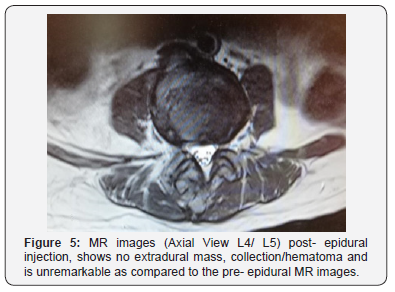

Her symptoms however continued to persist even after 24 hours to which an MRI was done to rule out epidural hematoma formation. The MRI reveals no extradural mass or hematoma collection. It was unremarkable as compared to the pre- epiduralinjection MR images (Figure 4-6). All other blood investigations and imaging was also normal. She subsequently underwent an emergency laminectomy of the L4/L5 and L5/S1 level after 6 days of observation for spontaneous neurological recovery. Intraoperative findings reveal no hematoma and upon laminectomy, the dura bulge outwards (Figure 7).